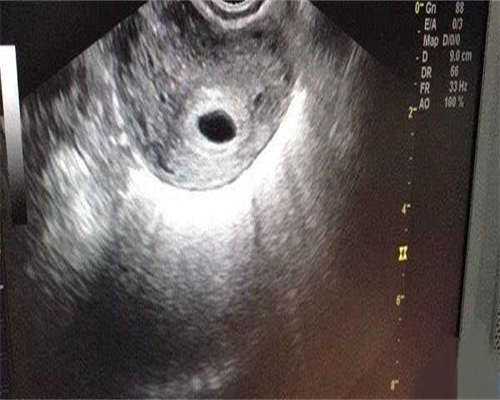

我b超做了有卵黄囊,hcg9天翻倍到18166,就是孕酮小单位才16.7,现在也好担心

我孕五周,查出孕囊没看到胎心胎芽呕吐头晕太厉害了,现在不打算吃了,就静卧休息,反正也没见红也不痛